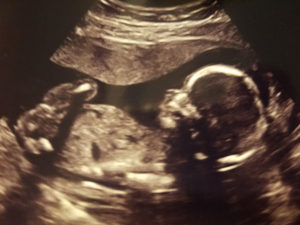

I am currently 22 weeks pregnant and expecting a baby girl due April 22nd. My C-Section date will be scheduled on my next visit.